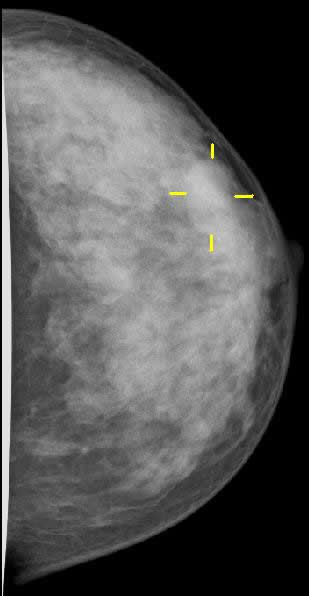

Einen speziellen Schwerpunkt unserer Praxis stellt die Mammadiagnostik dar. Wir bieten Ihnen die Möglichkeit einer umfangreichen Brustdiagnostik durch Mammographie und Mammasonographie.

Brustkrebs ist in Deutschland die häufigste Krebsart bei Frauen. Jede achte bis zehnte Frau erkrankt in ihrem Leben an Brustkrebs. Durch konsequente Früherkennung kleinerer, nicht tastbarer Tumore kann die Überlebensrate bei Brustkrebs deutlich gesteigert werden. Ab dem 30. Lebensjahr ist ein steter Anstieg von Brustkrebs zu verzeichnen.

Deshalb empfehlen wir den jährlichen Brustultraschall auf Wunsch als Vorsorge, den wir in unserer Praxis für Sie anbieten.

Bei fehlender familiärer Belastung mit Brustkrebs ist ab einem Alter von 40 Jahren eine regelmäßige Mammographie anzuraten. Gerne können Sie mit uns einen Termin für diese Untersuchung ausmachen.

Mammographie

Mammasonographie